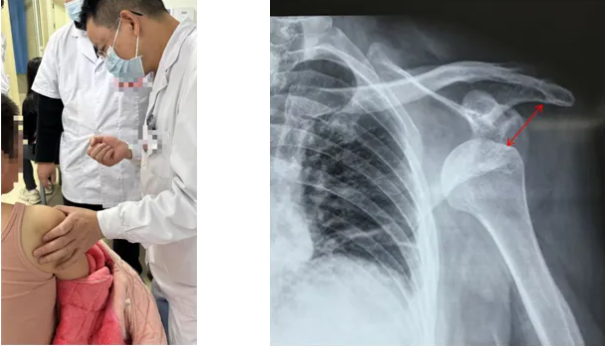

"大夫,我前段时间肩膀还不疼,这几天越来越痛,现在胳膊都抬不高了,不会是肩膀掉了吧?"脑卒中四周后的雷女士焦虑不已。

经系统评估,完善相关检查,康复医学科团队锁定原因,通过聚焦超声波治疗+良肢位管理+手法治疗,指导科学的肩部训练,在三周后她的肩关节活动度恢复至150°,疼痛基本消失。

肩关节半脱位(患侧肌肉无力致关节错位)